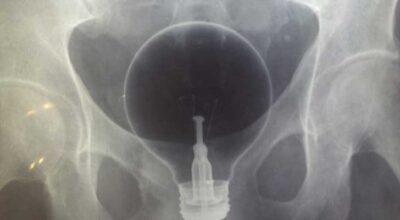

Esta recopilación de imágenes recoge alguna de las situaciones más estrambóticas que se han podido dar en una sala de rayos X. Todas ellas tienen algo en común: Son objetos extraños para el cuerpo humano que, de alguna manera han encontrado una vía de entrada, pero se han perdido a la hora de encontrar la de salida.

Muñecas de juguete descabezadas, botellas, armas, frascos, botes de plástico, teléfonos y hasta una cinta de casete pueden encontrarse en esa suerte de “punto limpio” al que ha quedado reducido el interior de los afectados.

No sabemos, ni juzgamos, la forma o los motivos por los que terminaron atrapados en dichas partes del cuerpo, pero estamos convencidos de que algún doctor estuvo al borde de la carcajada cuando se encontró con casos tan llamativos e inverosímiles como estos ¡Ver para creer!